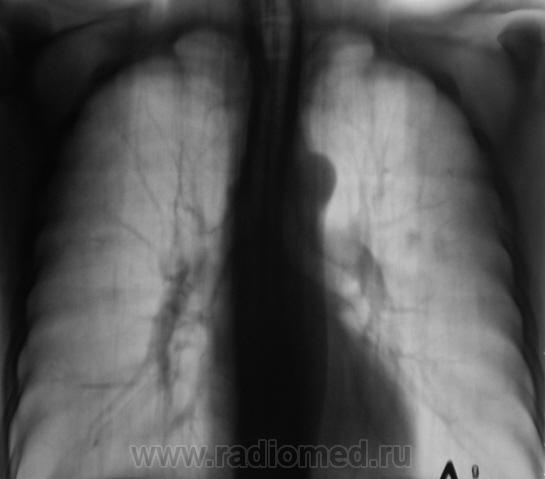

Рентгенограмма.

С двух сторон в верхних долях очаги. На вскидку tbs. А что с клиникой, анализами, анамнез.

Двусторонний очаговый туберкулез.

В s 1 -2 и глубоких отделах s6судя по срезам очаги,справа с включениями кальция,на фоне фоброзно измененного легочного рисунка

Скорее диссеминирмванный так как пораженно более 2-х сегментов.

Такое ощущение, что он свой ТБС уже пережил, возможно на ногах. Иногда фтизиатры пользуются термином - самоизлеченный ТБС ( возможно чуть по другому). А вот те тенюшки в левом легком - это то, что может вырасти в дальнейшем в какое-нибудь деонтологическое заболевание. Цепляться ли за них сейчас? Через год будет поздно. Мы такое уже проходили. И что-же делать?